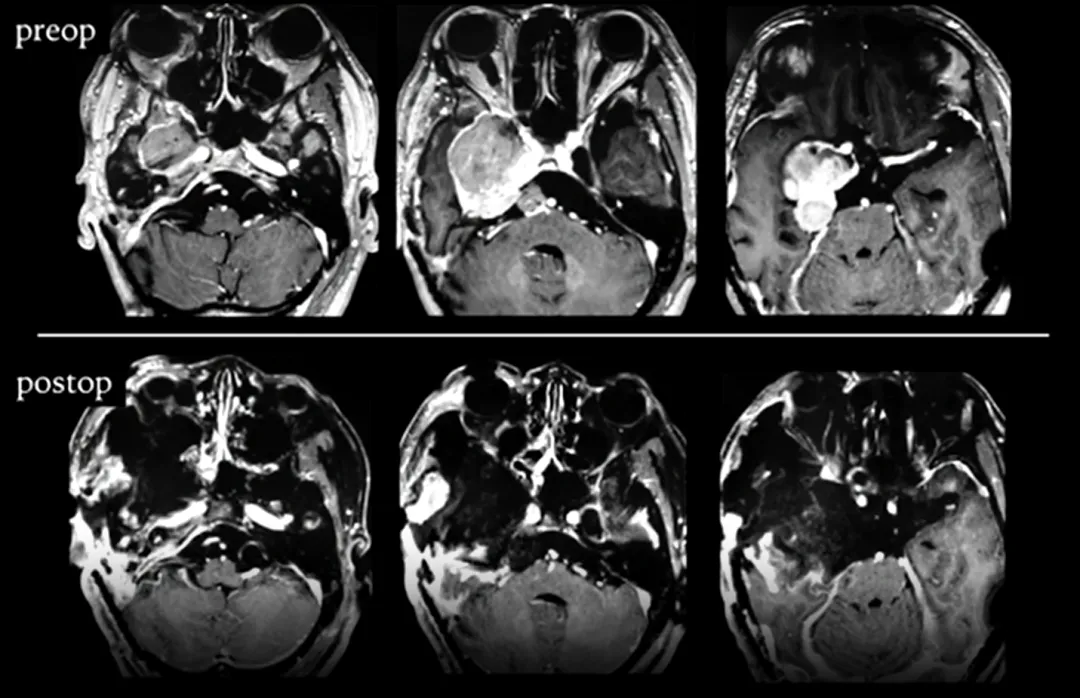

(A)首次手术的术前增强磁共振成像显示右侧巨大的海绵窦-岩斜区脑膜瘤,对脑干造成严重压迫。

(B)首次手术的术后磁共振成像显示右侧海绵窦有小的肿瘤残留(黄色箭头指示处)。

(C)第2次手术的术前磁共振成像显示海绵窦内残余部分肿瘤再生,并延伸至右侧后颅窝。

(D)第2次手术的术后磁共振成像显示右侧海绵窦仍有肿瘤残留(黄色箭头指示处)。

(E), (F)第3次手术的术前磁共振成像显示肿瘤侵袭性再生长。一个巨大的肿瘤占据右侧中颅窝,并向多方向延伸,并包绕了右侧海绵窦段颈内动脉。

第三次手术,术前术后影像